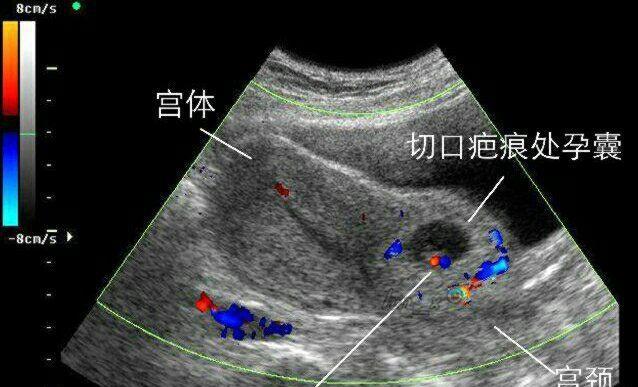

看!一胎剖腹,二胎危险!胚胎见缝就钻长在刀疤上

胚胎长在刀疤上,疤痕妊娠,我不堪回首的经历